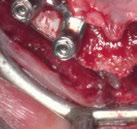

En las piezas 16 y 17 el paciente presentaba restauraciones atornilladas de metalcerámica sobre implantes oseointegrados. Se planificó realizar estas en una fase posterior a la rehabilitación de las piezas dentarias mediante flujo digital con bases de titanio y cuerpos de escaneo.

SW 5.2, Dentsply Sirona) (Figuras 22-27), la cual fue materializada en dos tipos de materiales a partir de bloques cerámicos IPS Empress CAD y cerámica vítrea de disilicato de litio IPS E.max CAD (Figuras 28-30)

Finalmente, las restauraciones se cementaron adhesivamente (Figuras 31-35). En las piezas 16 y 17 se realizaron restauraciones cementoatornilladas como última fase de tratamiento. Se recomendó al paciente una férula de protección superior la cual fue elaborada mediante un flujo de trabajo digital (Figura 36)